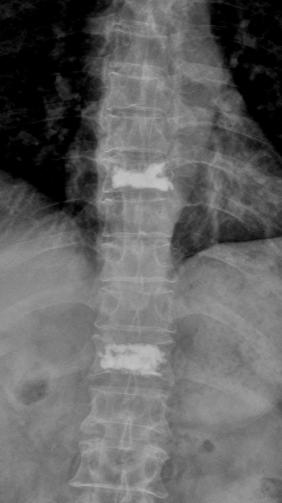

术前核磁共振检查明确T8.12椎体骨折,为疼痛责任椎体;经皮穿刺微创椎体成形术后复查可见椎体高度恢复良好,骨水泥弥散满意。

术前过伸位X、CT检查,早期诊断